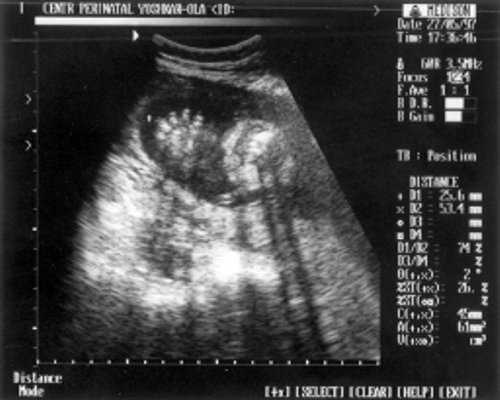

- ДБ (длина бедра) = 24 мм - 17 нед. (рис. 2)

Рис. 2. УЗИ плода - бедро.